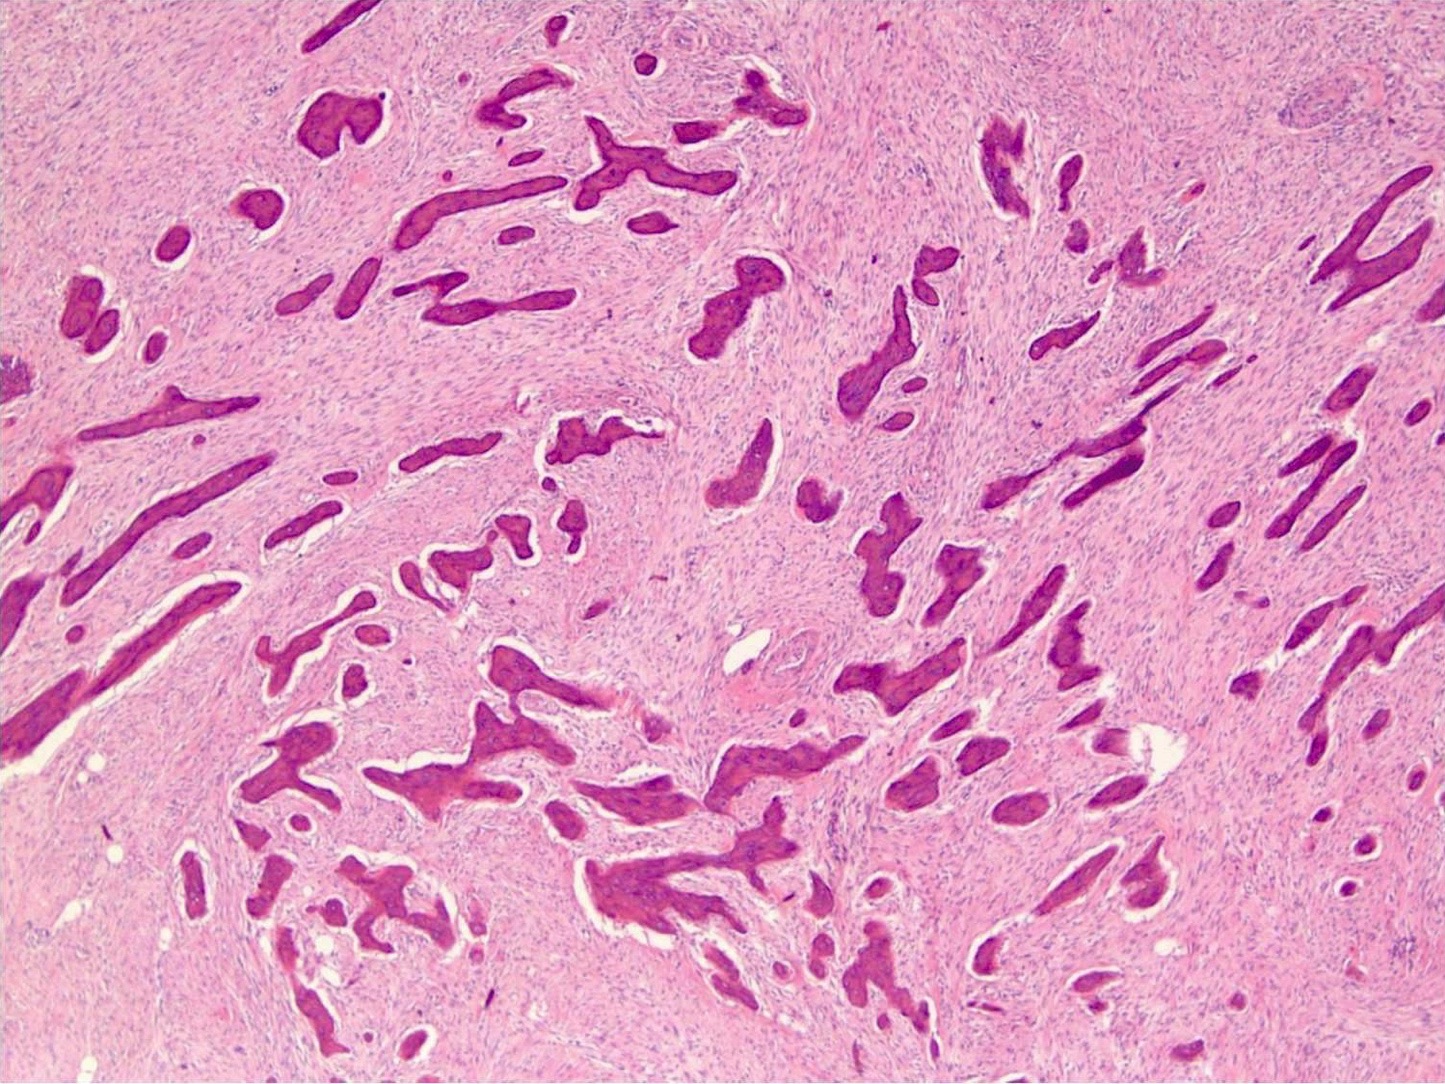

- Low grade central osteosarcoma:

- Permeative growth:

- Intramedullary (surrounds and erodes native trabeculae, fills Haversian systems)

- Cortical destruction and soft tissue invasion

- Neoplastic cells: fibroblast-like spindle cells (minimal atypia); hypocellular to moderately cellular

- Scattered mitoses may be seen

- Arranged in fascicles or interlacing bundles

- Neoplastic bone:

- Bone trabeculae (fibrous dysplasia-like): curved, branching or interanastomosing

- Longitudinal lamellar bone: like parosteal osteosarcoma

Microscopic (histologic) images

Contributed by Jesse Hart, D.O., Borislav A. Alexiev, M.D. and AFIP

A 12 year old girl has a 10.5 cm intramedullary mass in the distal femur, which was resected (see gross and microscopic images). High power views demonstrate bland spindle cells. Which of the following is most accurate regarding this tumor?

A. Most likely, genetic abnormality is amplification of the MDM2 gene. The tumor is a low grade central osteosarcoma.